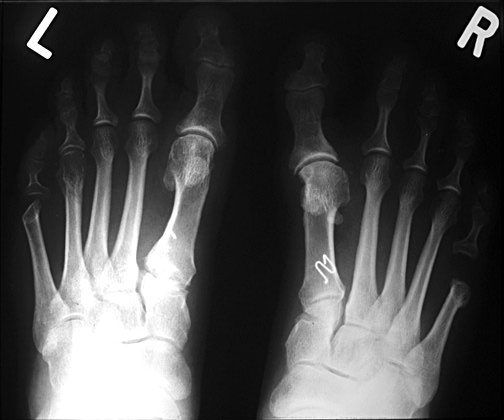

BilatHV:

This patient has a marked hallux valgus deformity in both feet. As the first toe migrates more and more to valgus, it presses against the second toe, and may aggravate dorsal clawing of the second toe, which is usually initiated by overload of the second metatarsal and synovitis of the metatarsophalangeal joint. Also note the relative hyperostosis of the second metatarsal shafts compared to the third and fourth, as well as dorsal rotation of the fibular sesamoids.

PreOp:

Preoperative film showing hallux valgus and clawtoe deformities of the second and third toes. Medial subluxation of the head off the sesamoids is shown, as well as marked hyperostosis of the second metatarsal shaft.

PostOp:

Same patient status post Lapidus procedure. With osteotomy of the 1st metatarsal, the 1st metatarsal head has been realigned in a more lateral and plantar location over the sesamoids. The 1st tarsometatarsal joint has been fused. Kirschner wires are seen in the 2nd and 3rd toes after osteotomy for clawtoe deformities.